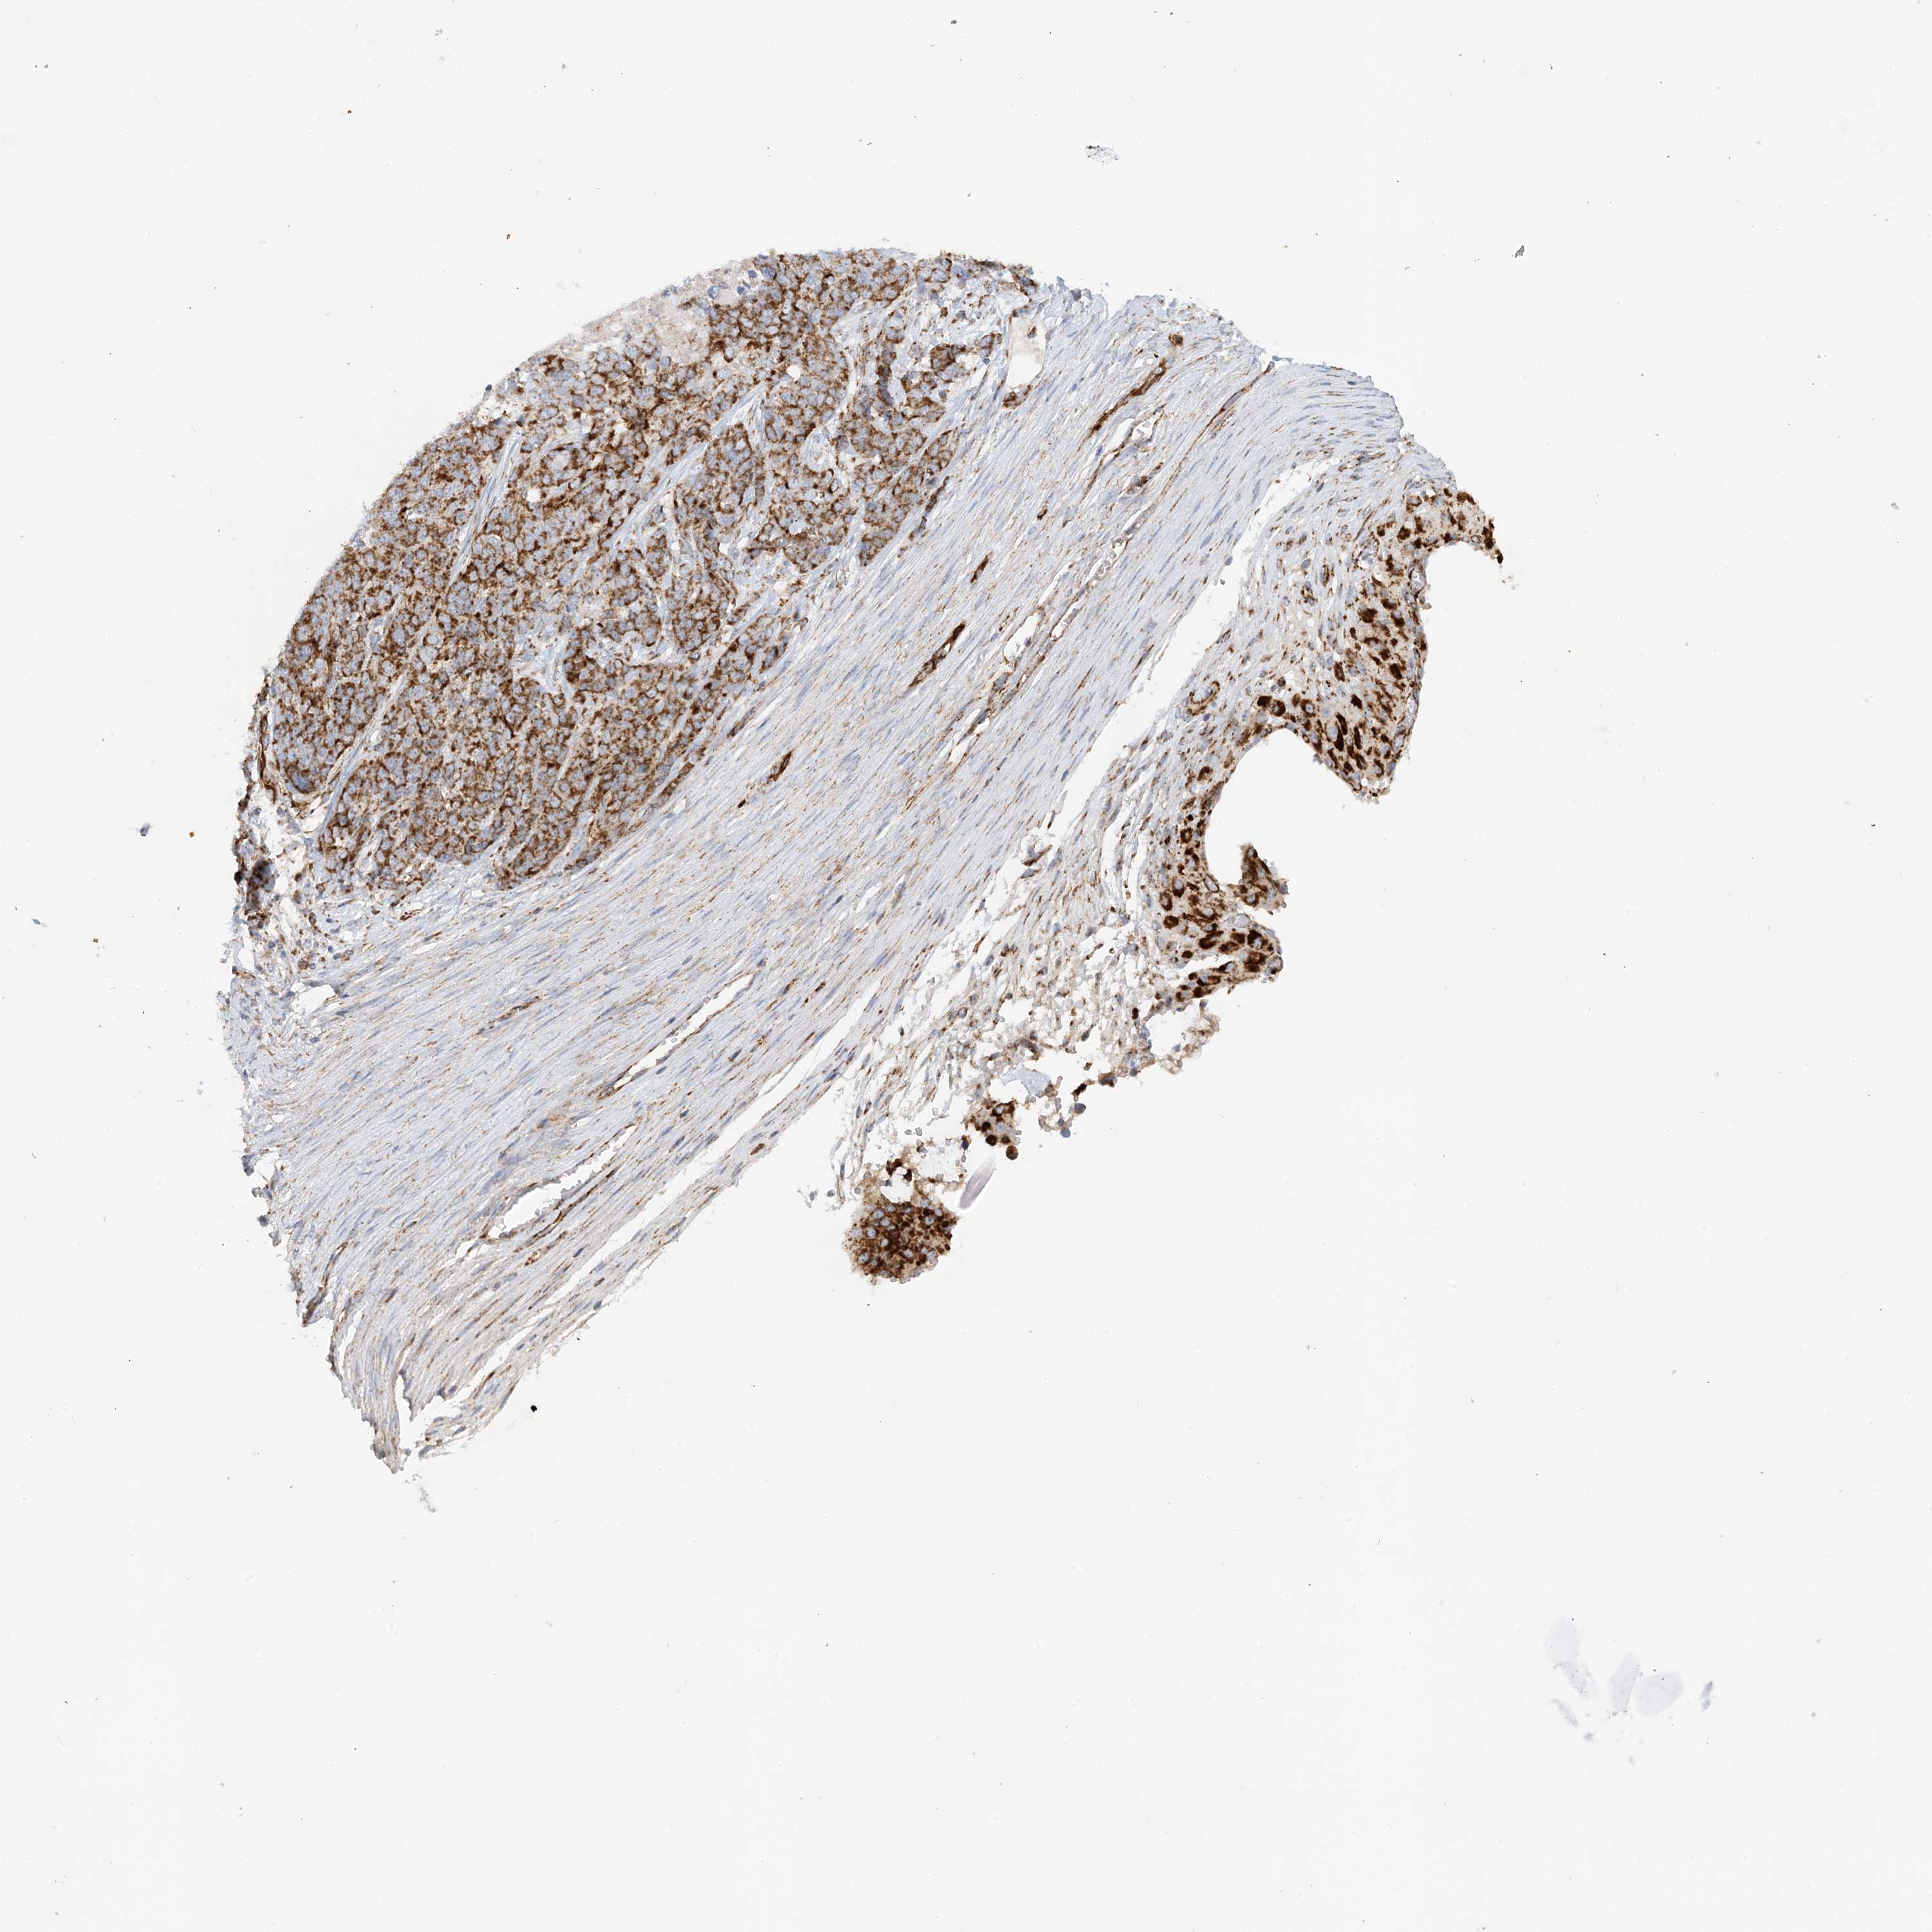

OVARIAN CANCER - Protein expressioni

A mouse-over function shows sample information and annotation data. Click on an image to view it in a full screen mode. Samples can be filtered based on level of antibody staining by selecting one or several of the following categories: high, medium, low and not detected. The assay and annotation is described here.

Note that samples used for immunohistochemistry by the Human Protein Atlas do not correspond to samples in the TCGA dataset.

Antibody stainingi

Antibody staining in the annotated cell types in the current human tissue is reported as not detected, low, medium, or high, based on conventional immunohistochemistry profiling in selected tissues. This score is based on the combination of the staining intensity and fraction of stained cells.

Each image is clickable and will lead to virtual microscopy that enables deeper exploration of all samples and also displays staining intensity scores, fraction scores and subcellular localization as well as patient and tissue information for each sample.

Antibody HPA031966

Cystadenocarcinoma, serous, NOS

Carcinoma, endometroid

Cystadenocarcinoma, mucinous, NOS

Carcinoma, NOS